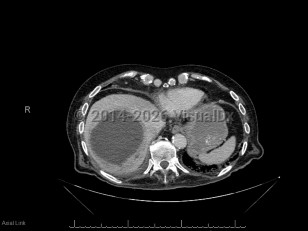

Pyogenic liver abscessPyogenic liver abscess